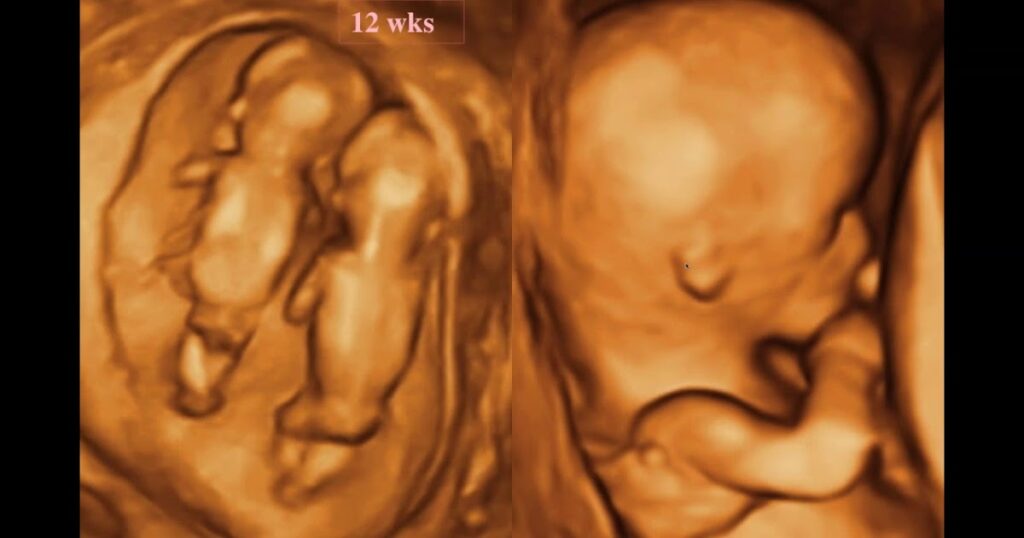

The Anomaly Scan, often called the “20-week scan” or “mid-pregnancy scan,” is a more detailed examination performed in the second trimester.

- Timing: This ultrasound is typically scheduled between 18 and 22 weeks‘ gestation.

- Purpose: Unlike the NT scan, which assesses genetic risk, the anomaly scan is a structural check. It provides a detailed overview of the baby’s physical development, examining organs such as the heart, brain, kidneys, and spine. It checks for physical abnormalities such as cleft lip, spinal defects, or heart issues, and also confirms the position of the placenta.